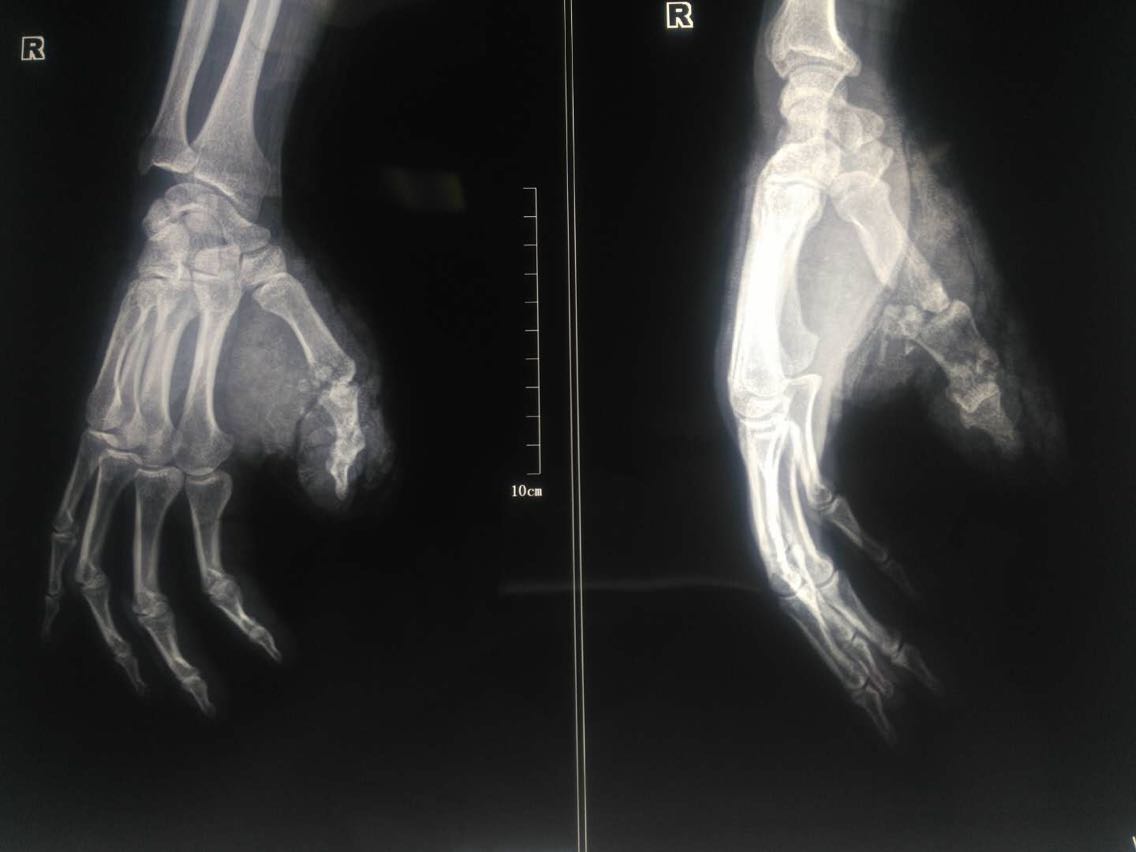

查体:右手背桡侧可见一长约5cm斜行裂伤,周围软组织肿胀,右手拇指远端感觉稍麻木。右手拇指活动明显受限。 辅助检查: 手部正斜位X片示:右侧第一掌骨中段及远端粉碎性骨折。

患者男性,49岁。 主诉:电锯锯伤致右手疼痛出血26+小时。 现病史:26+小时前患者工作时不慎被电锯锯伤致右手背桡侧疼痛伴出血,伴右手拇指远端皮肤感觉稍麻木,无其他特殊不适。就诊于当地医院查手部正斜位X片示:右侧第一掌骨中段及远端粉碎性骨折。给予简单消毒包扎后转诊至我院急诊,急诊以“右手第一掌骨远端、拇指近节指骨开放性骨折”收入我科。 既往史无特殊。